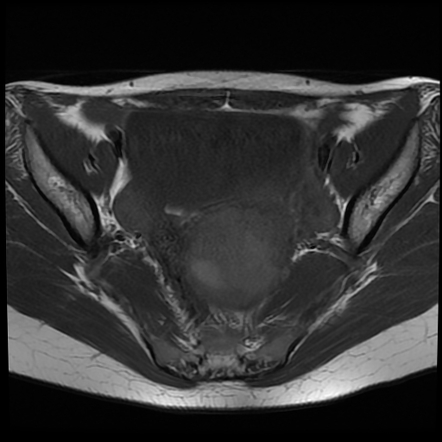

uterine leiomyomas radiopaedia radiology t2

Myxoid Uterine Leiomyoma | Image | Radiopaedia.org

radiopaedia.org

radiopaedia.org

Myxoid Uterine Leiomyoma | Image | Radiopaedia.org

radiopaedia.org

radiopaedia.org

Myxoid Uterine Leiomyoma | Radiology Case | Radiopaedia.org

radiopaedia.org

radiopaedia.org